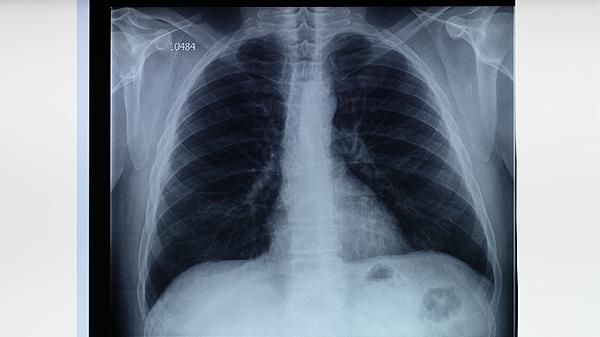

預(yù)防肺結(jié)核需保持均衡飲食與規(guī)律作息,避免與咳嗽患者密切接觸。居住環(huán)境應(yīng)定期開(kāi)窗通風(fēng),免疫力低下者可咨詢(xún)醫(yī)生預(yù)防性用藥。出現(xiàn)午后低熱、痰中帶血等癥狀時(shí),須立即到傳染病專(zhuān)科醫(yī)院進(jìn)行結(jié)核菌素試驗(yàn)、胸部CT等檢查。治療期間嚴(yán)格按時(shí)服藥6-8個(gè)月,不可自行停藥以防產(chǎn)生耐藥性。